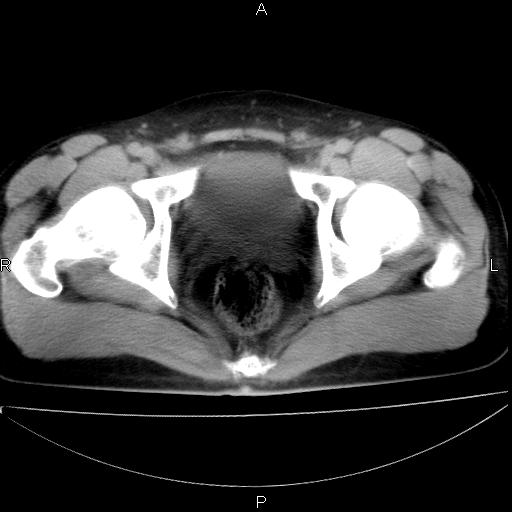

男 25岁 自述 尿频尿急,排尿困难20多天.无腰痛, b超说左肾盂轻度积水,左输尿管上端扩张.未见结石影. ct我看双侧肾盂轻度积水,双输尿管上端都扩张,大家看看能看见结石吗?

双肾轻度积水,双侧输尿管上段扩张(原因待查)。

双输尿管扩张下端未见高密度结石和输尿管晕轮征,不好说是结石.增强后如何?

双肾轻度积水,未见明确结石,薄层对结石检出率较高。

双肾盂及双输尿上段轻度积水,双输尿管未见明显结石影。